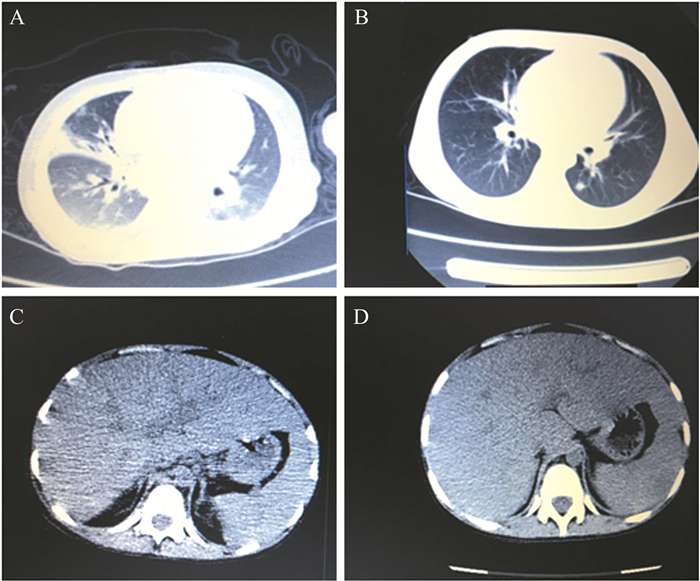

胸部CT示双肺感染性病变,双侧胸腔积液(图 3A)。腹部CT示肝大伴回声改变,脂肪肝, 胆囊壁水肿,脾大,脾内多发低回声团,腹膜后多发淋巴结肿大,腹腔积液(图 3C)。

图 3 一例艾滋病合并马尔尼菲青霉败血症患儿的胸部及腹部CT检查结果 A:抗真菌治疗前的胸部CT检查结果,示肺部感染病灶注;B:抗真菌治疗后的胸部CT检查结果,示肺部病灶较前基本吸收;C:抗真菌治疗前的腹部CT检查结果,示肝脏脂肪变性;D:抗真菌治疗后的腹部CT检查结果,示患儿肝脏脂肪变性好转 |